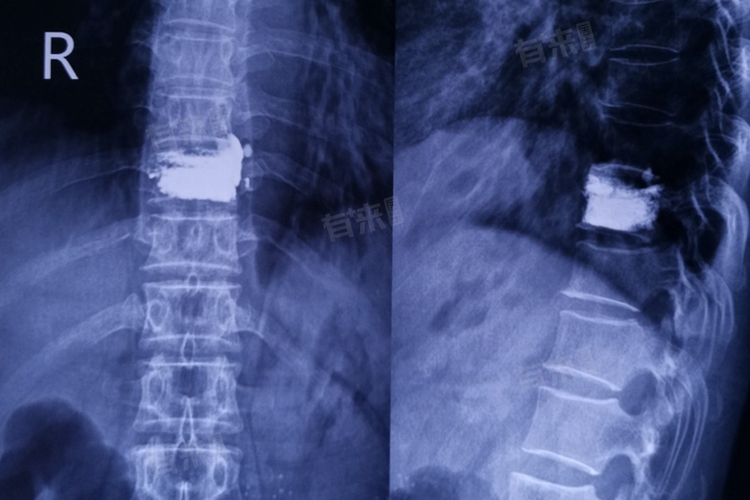

- 椎弓根钉内固定:手术治疗一般采用椎弓根钉内固定的方法,可以有效地将胸椎复位,恢复椎体的稳定性和高度。

- 切开复位内固定术:对于中青年患者,如果胸腰椎压缩的程度严重,可能需要进行切开复位内固定术,让压缩的椎体恢复正常高度,有利于恢复正常的脊柱序列。

- 植骨术:在某些情况下,为了促进骨折愈合和恢复椎体高度,可能需要进行植骨术。